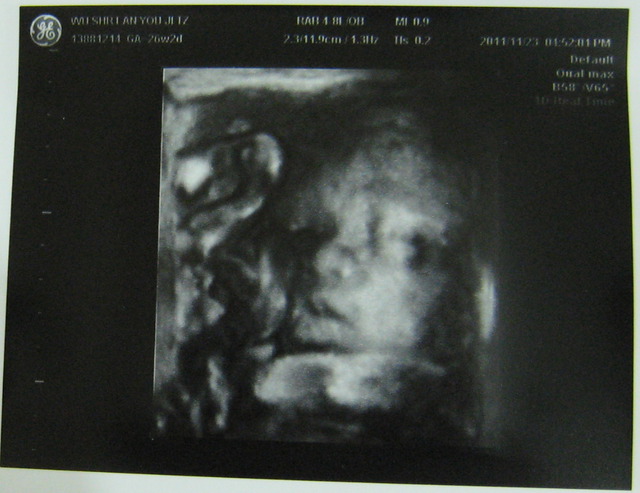

有,次也做4D,然我看到的是模糊的影像,但有次看到瓦力正在打哈欠?的子,我得好好玩,也很多人有看胎在肚子打哈欠(嘴巴)的子,所以跟大家分享。往下看就找到喔。